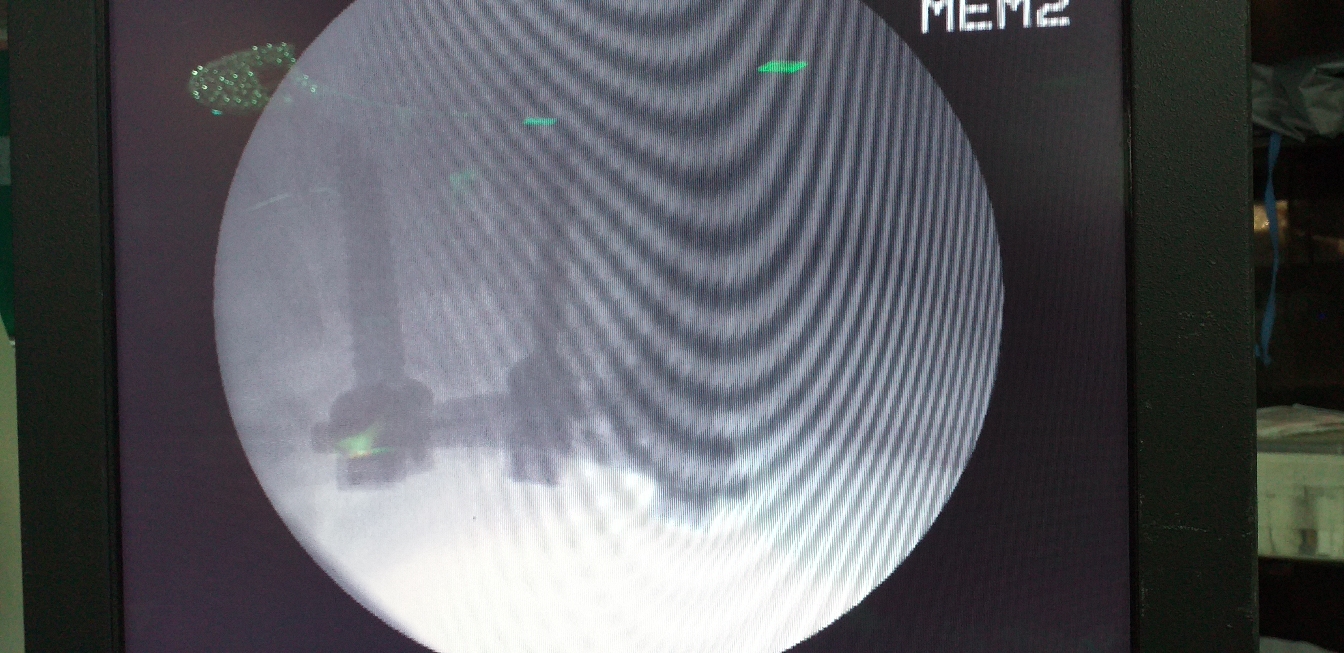

Multiple level Lumbar Spine Fusion. Complete Relief from Pain